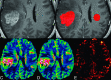

Background and purpose: Contrast leakage results in underestimation of the CBV of brain tumors. Our aim was to compare the diagnostic performance of DSC perfusion MR imaging without and with mathematic contrast-leakage correction in differentiating PCNSLs and glioblastomas.

Materials and methods: Perfusion parameters-CBV, corrected CBV, and leakage coefficient-were measured in enhancing tumor portions and contralateral NAWM of 15 PCNSLs and 20 glioblastomas, respectively. The ratios of CBV and corrected CBV were calculated by dividing the tumor values by those obtained from contralateral NAWM. A paired t test was used to compare tumor K2 and NAWM K2, as well as tumor CBV ratios without and with leakage correction. Comparisons of CBV, corrected CBV, and K2 between PCNSLs and glioblastomas were done by using a 2-sample t test. The diagnostic performance of DSC perfusion MR imaging without and with contrast-leakage correction was assessed with receiver operating characteristic curve analysis.

Results: PCNSLs and glioblastomas demonstrated higher K2 than those in their contralateral NAWM. Corrected CBV ratios were significantly higher than the uncorrected ones for both tumors. PCNSLs had lower CBV ratios (P < .001), lower corrected CBV ratios (P < .001), and higher K2 (P = .001) compared with glioblastomas. In differentiating between PCNSLs and glioblastomas, the area under the curve of the CBV ratio, corrected CBV ratio, and K2 were 0.984, 0.940, and 0.788, respectively.

Conclusions: PCNSL can be differentiated from glioblastoma with CBV ratios, corrected CBV ratios, and K2. CBV without contrast-leakage correction seems to have the best diagnostic performance in differentiating the 2 tumors.